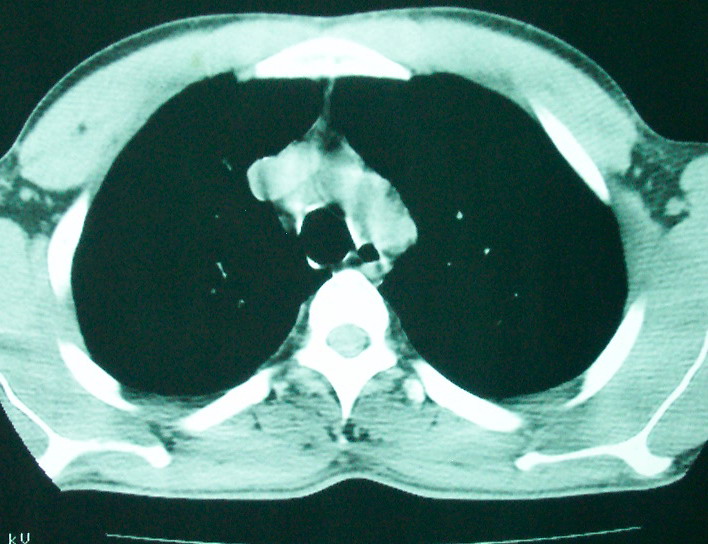

空洞内可见小结节样密度影考虑合并真菌感染

我看是不是可以两元化来解释,左肺下叶还是肺脓疡,而其余病灶考虑肺癌伴肺内转移,我看右肺上叶尖段病灶可见明显毛刺改变为原发病灶.

1、左下肺鳞癌伴两肺及纵隔淋巴结转移;

2、两上肺支扩伴慢性炎症。

左下肺病灶除了明显的厚壁空洞 气液平外,明显见壁结节,另两肺多发小结节,综合考虑:左下肺周围性肺癌伴肺内转移.

鳞癌肺肺转移:厚壁空洞,洞壁厚薄不均,内似有壁结节,肺脓肿临床有无提示,血像如何?病灶周围很干净,没有明显渗出,很勉强?